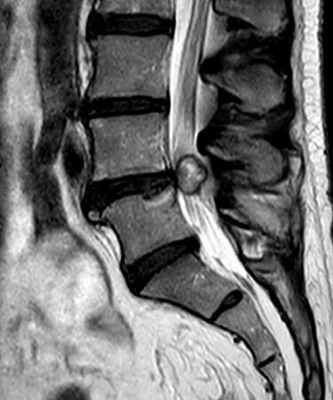

На Т1-зависимых МРТ позвоночника киста имеет ликворную интенсивность сигнала и проявляется только масс-эффектом. На Т2-зависимых МРТ позвоночника она может иметь неоднородный сигнал в связи с движением ликвора. Контрастное вещество не накапливает. Форма кисты округлая, контур, если прослеживается, четкий ровный .

МРТ позвоночника. Т2-взвешенная сагиттальная МРТ. Арахноидальная киста.